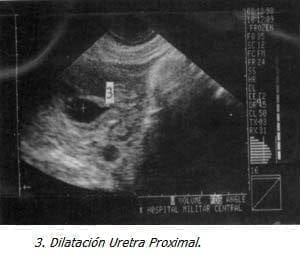

La uropatía obstructiva secundaria a valvas de la uretra posterior, tiene una presentación clínica variable y a menudo insidiosa, la obstrucción causada por repliegues de mucosa que obstruyen la uretra origina la patología, ocurre solo en hombres y tiene un amplio espectro de características ecográficas cuyos signos cardinales son dilatación persistente de vejiga y la porción proximal de la uretra con engrosamiento de la pared vesical (2, 10).

Con Impresión Diagnóstica de dolor abdominal a estudio y embarazo de 18 semanas se realiza ecografía obstétrica que evidencia feto único, vivo, con biometría para 18 semanas, ausencia del líquido amniótico y distensión abdominal importante. Se realizó ecografía de detalle previa cordocentesis para cariotipo y amnioinfusión de SSN, observando marcada ascitis, dilatación vesical importante con engrosamiento de la pared y dos soluciones de continuidad, dilatación de la uretra proximal y aumento de tamaño e hiperecogenicidad renal bilateral, los ureteres no se evidenciaron excepto en la unión vesicoureteral. El resultado del estudio genético confirmó sexo masculino (46XY) sin ninguna malformación genética asociada.

La obstrucción del nivel uretral secundario a valvas posteriores tiene un amplio espectro de características ecográficas y los signos cardinales consisten en dilatación persistente de la vejiga y la porción proximal de la uretra, engrosamiento de la pared vesical mayor de 2mm, los uréteres están característicamente dilatados y tortuosos y en casos severos su entrada a la vejiga se observa (10-15).